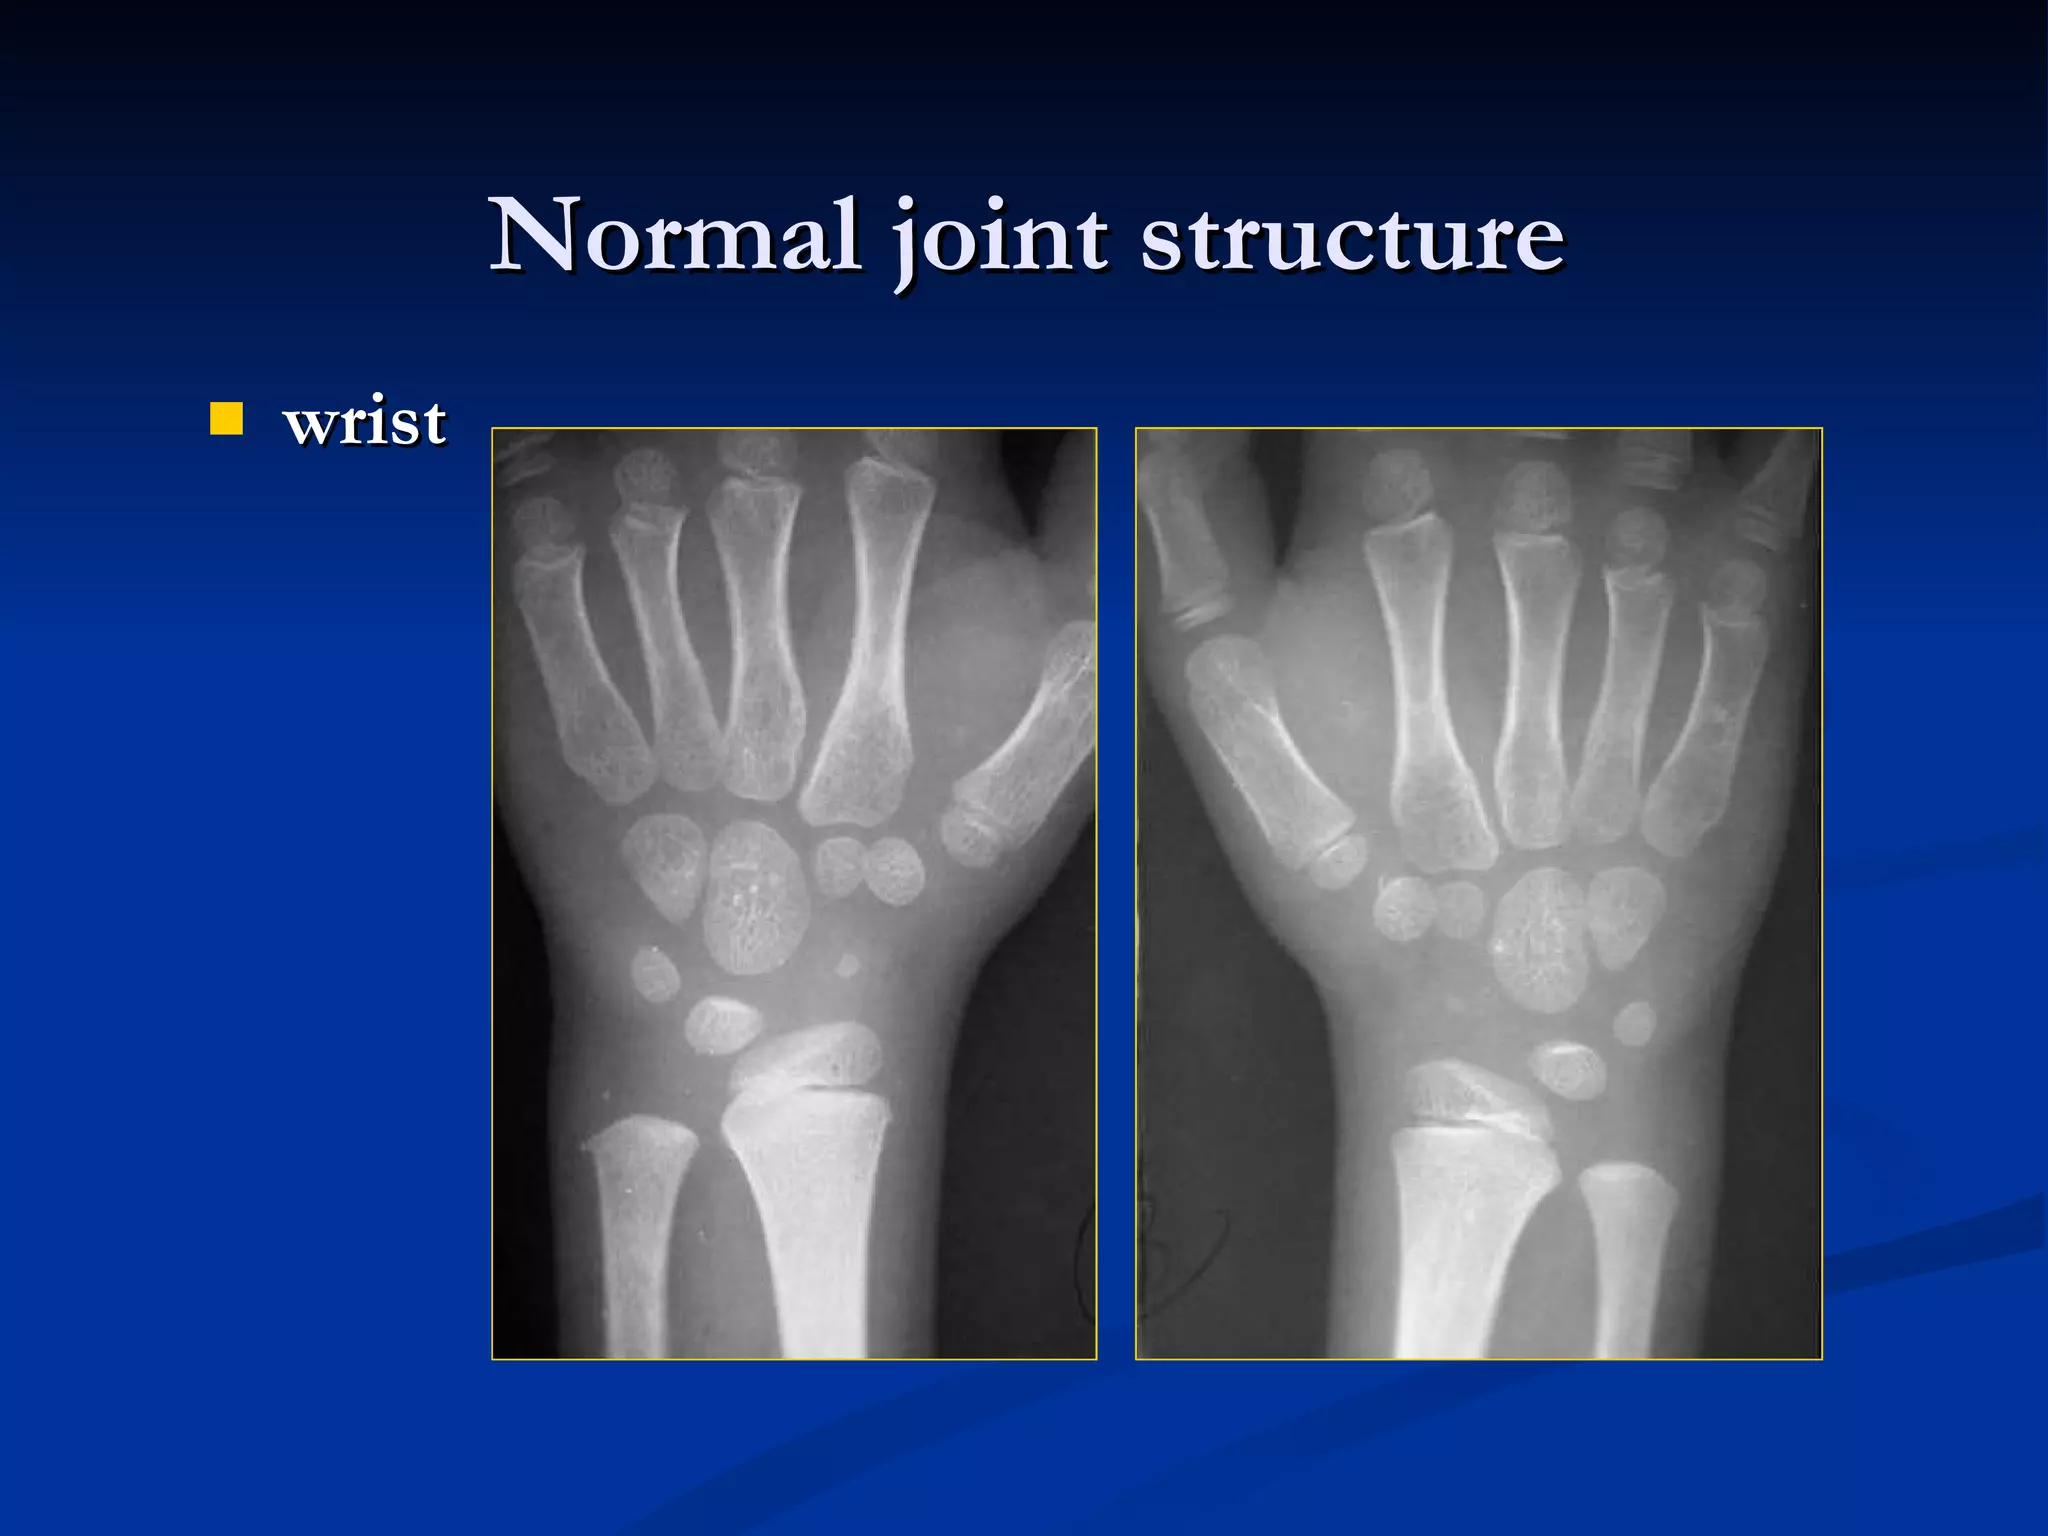

wrist Normal joint structure